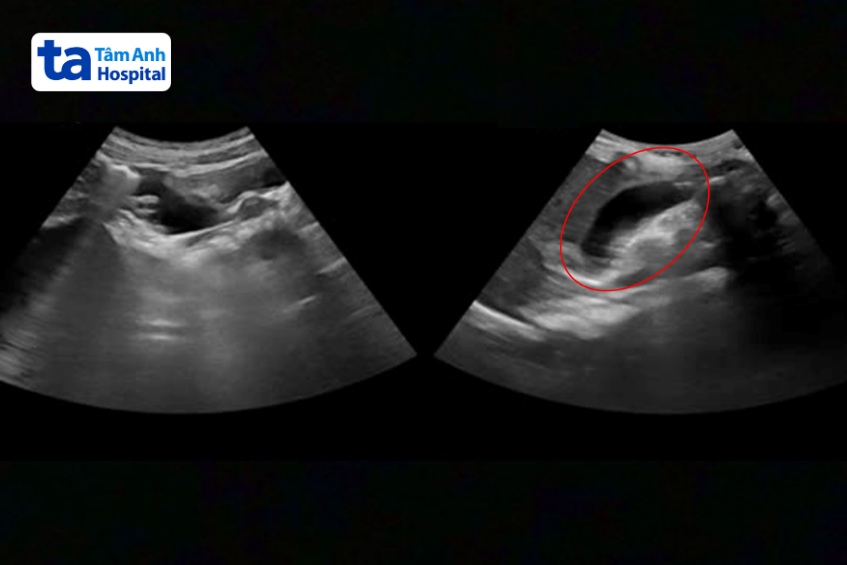

Kết quả xét nghiệm máu cho thấy chỉ số bạch cầu của bé là 13.000/mm3, bình thường 4.000-10.000/mm3 máu. Siêu âm đường kính ruột thừa 10-12mm kèm sỏi phân trong lòng ruột thừa, còn bình thường đường kính dưới 6mm.

“Bé Trang viêm ruột thừa có thể do sỏi phân bị kẹt ngay chỗ nối giữa ruột thừa và manh tràng”, bác sĩ Vũ thông tin.